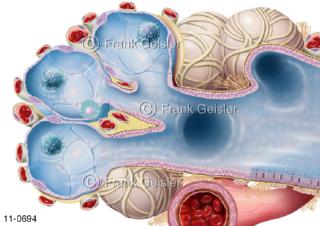

11-0694 Aufbau Lobulus in Lunge, Lungenbläschen Alveoli mit Blutkapillare